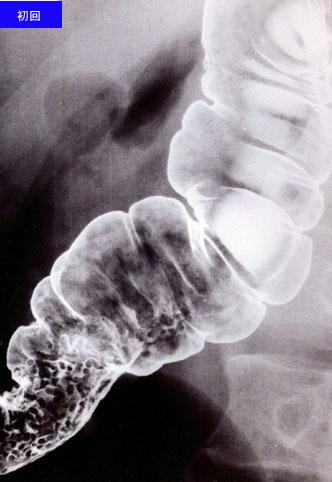

疾患(病理主体)の分類炎症性・潰瘍性疾患/クローン病

部位(臓器別)大腸/横行

検査方法X-P